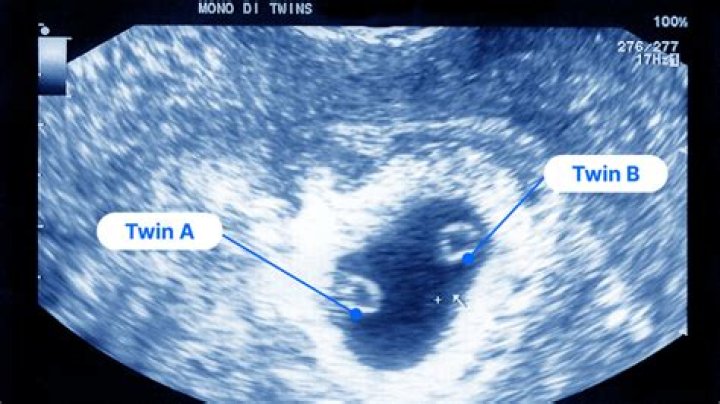

Can there be a yolk sac and no baby?

A pregnancy is anembryonic if a transvaginal ultrasound reveals a sac with a mean gestational sac diameter (MGD) greater than 25 mm and no yolk sac, or an MGD >25 mm with no embryo.

The gestational sac is the large cavity of fluid surrounding the embryo. During early embryogenesis it consists of the extraembryonic coelom, also called the chorionic cavity. The gestational sac is normally contained within the uterus.

In viable pregnancies, a trans-vaginal (internal) scan should be able to detect a gestation sac from 5weeks of pregnancy. A yolk sac can be seen at 5 1/2 weeks and fetal pole (small embryo) seen at approximately 6 weeks.